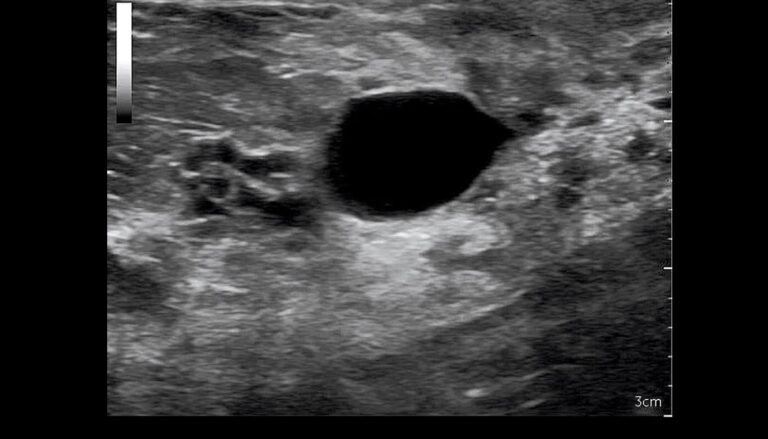

O que significa BI-RADS®?

BI-RADS® é um acrônimo para Breast Imaging-Reporting and Data System®, uma classificação desenvolvida inicialmente para ser utilizada com…